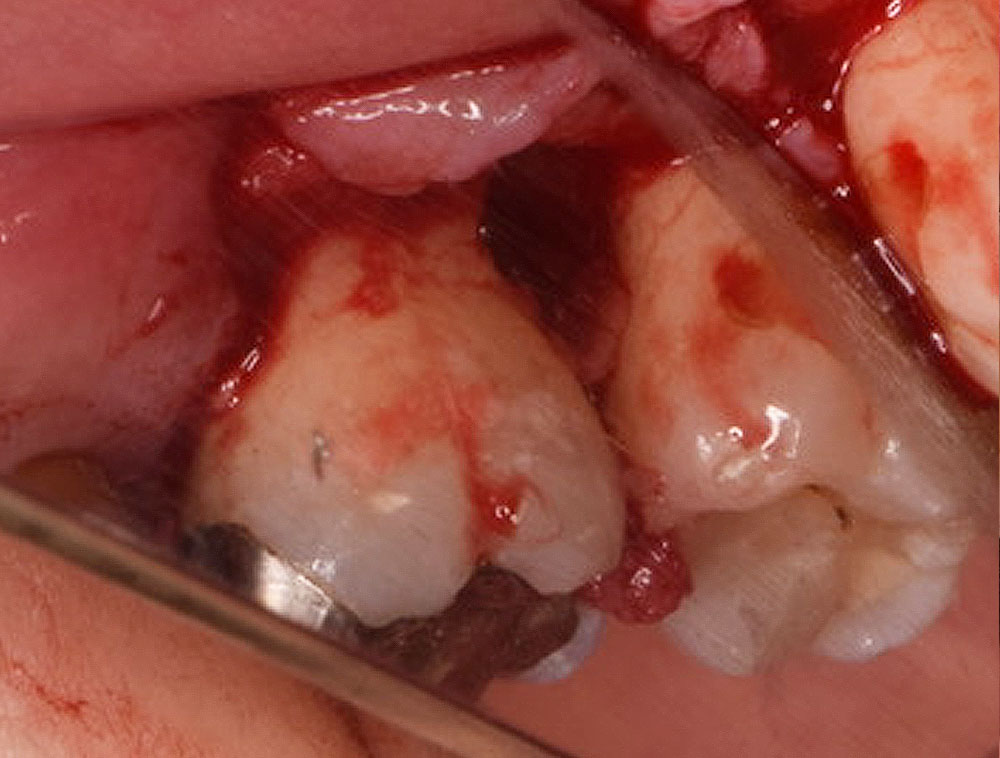

治療ステップ3歯周再生療法

EMD による再生治療は外科的なアプローチをともない行います。まず歯肉を切開・剥離して歯根と歯槽骨を見えやすい状態にします。この状態でそれまで(歯肉縁下の)歯茎に隠れていた歯根先端部についた歯石、歯周病に感染したセメント質を清掃・除去します。